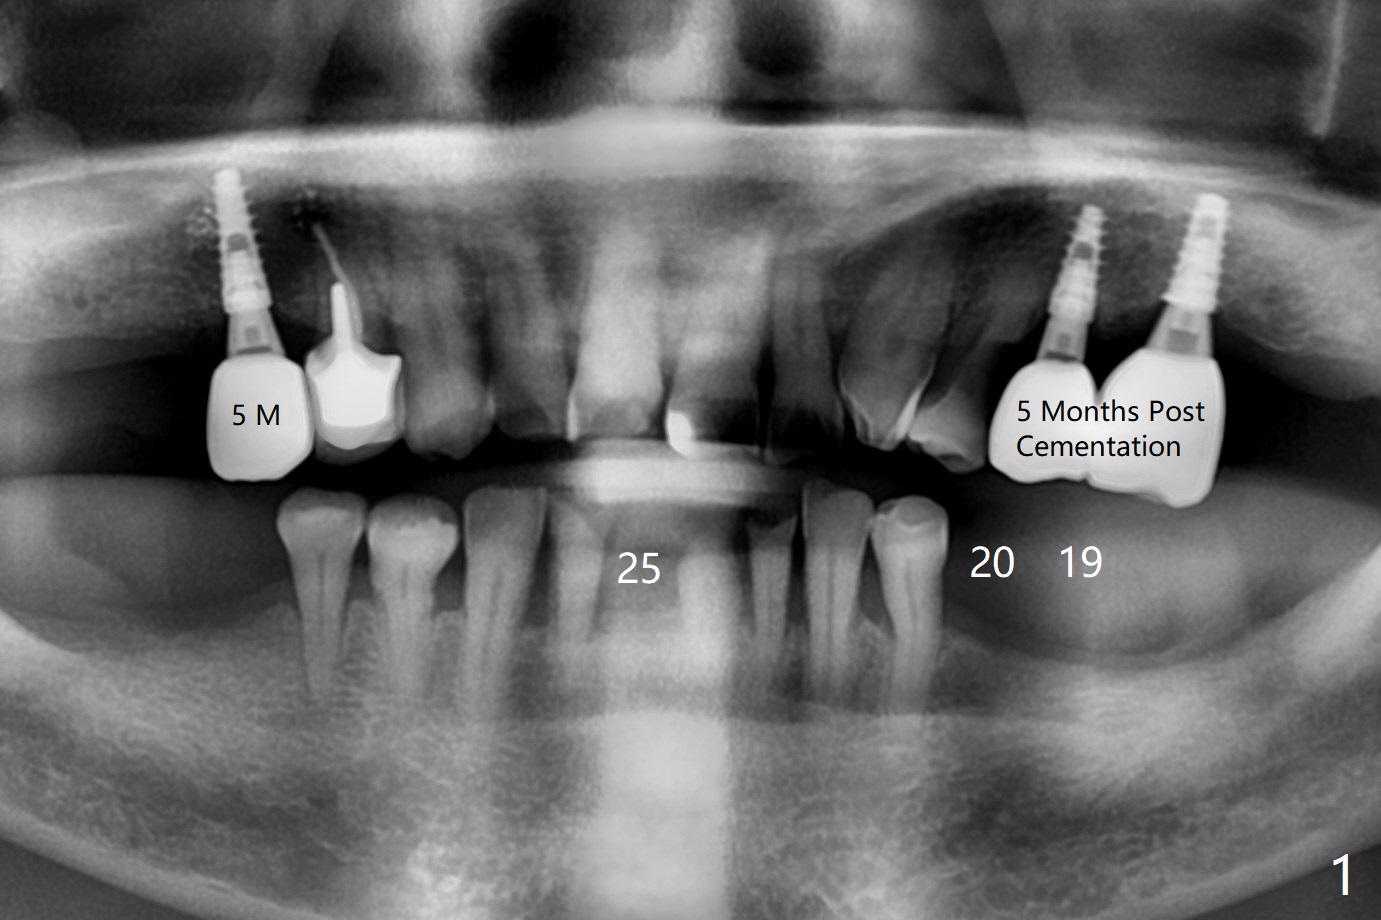

A 67-year-old man requests lower implants (19,20,25) to replace lower RPD with history of food impaction under the partial 5 months post cementation of the upper implants (Fig.1). Due to the atrophic mandible, 1-piece implants will be placed with guide (Fig.2-5) and free hand (Fig.6). Incision will be made at all of the sites for vision and bone graft.